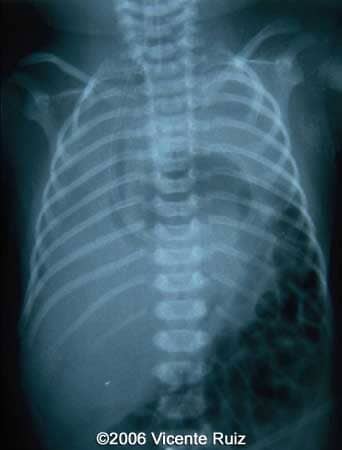

Chest radiography immediately after birth: gastric probe into the left hemithorax

Autopsy. Left hemithorax occupied by abdominal organs: stomach, colon, appendix, left hepatic lobe, spleen.